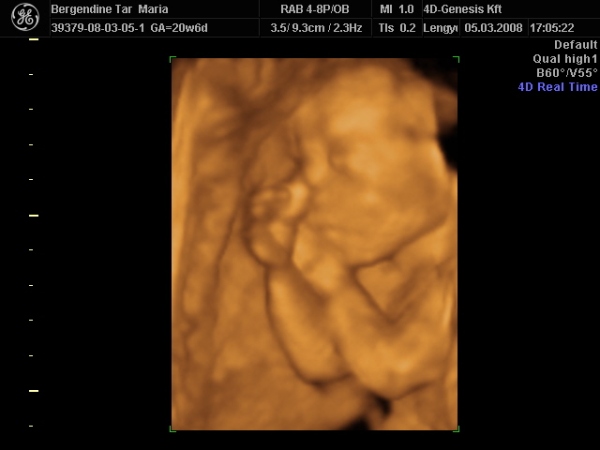

Hazaértem az ultrahangról, bemutatom nektek Zsófit:

Kép

édes a babád! Olyan mintha szopná az ujját, nem? :) A lányomnál már a 12 hetes ultrahangon úgy nézett ki, mintha szopná az ujját, aztán amikor megszületett, az első naptól kezdve szépen szabályosan szopta a hüvelykujját! Akkor lehet hogy mégis volt már gyakorlata benne???

Igen, a vizsgálat alatt csak néhány képen nem tömi az ujját a szájába. :lol:

végig ezzel volt elfoglalva. :lol: :lol: